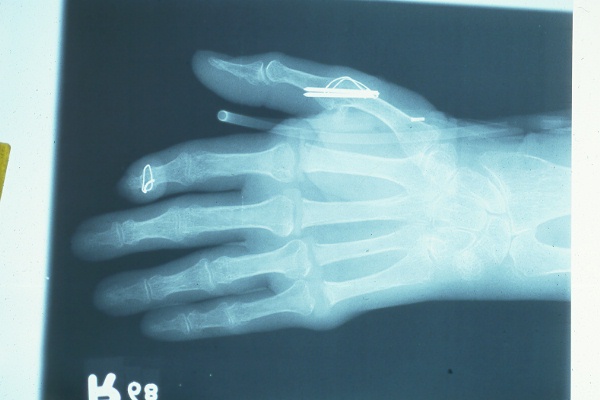

Preop films.